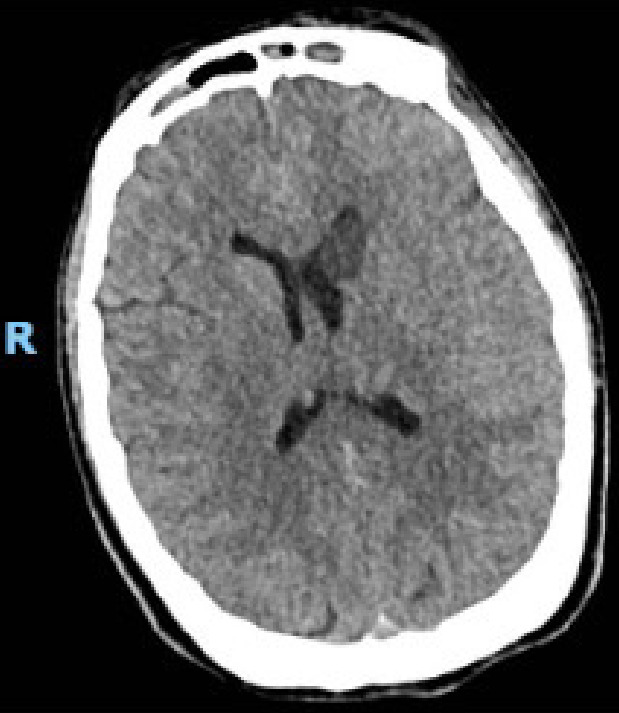

垂体手术后脑缺血并发症的报道并不多见。多种机制被提出,包括术后蛛网膜下腔出血引起的血管痉挛和延迟性脑缺血。鉴于这些情况下血管痉挛的病因不明,对其预防知之甚少。通过一份病例报告和文献回顾,作者警告术后识别可能表明脑血管痉挛风险增加的关键体征的重要性,必须及时识别,一旦出现这些症状就采取适当的治疗策略。

Cerebral ischemic complications after pituitary surgery are not frequently reported. Multiple mechanisms have been proposed, including vasospasm, and delayed cerebral ischemia resulting from postoperative subarachnoid bleeding. Given the unknown etiology of vasospasm following these situations, little is known about its prevention. Through a case report and bibliographic review, the authors warn about the importance of recognizing key signs postoperatively that could indicate increased risk for cerebral vasospasm and must be recognized in a timely manner, with appropriate treatment strategies implemented once these symptoms present.